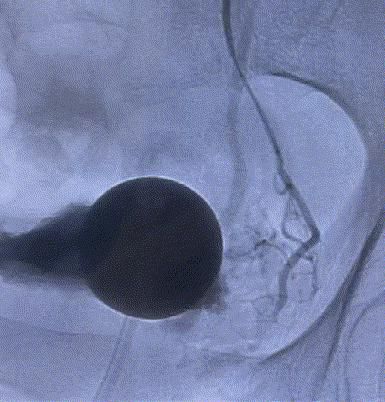

随後,李旭丹主任攜手胡志華主任爲患者實施介入治療,采用改良Seldinger法穿刺股動脈,在DSA引導下經動脈自然腔道,将微導管分别送達雙側髂内動脈進行造影,觀察雙側前列腺動脈分布情況,将微導管超選擇至雙側前列腺動脈,準确置入PVA栓塞材料,成功阻斷前列腺的營養供給,順利完成了治療。

△術後,前列腺供血動脈被成功阻斷。